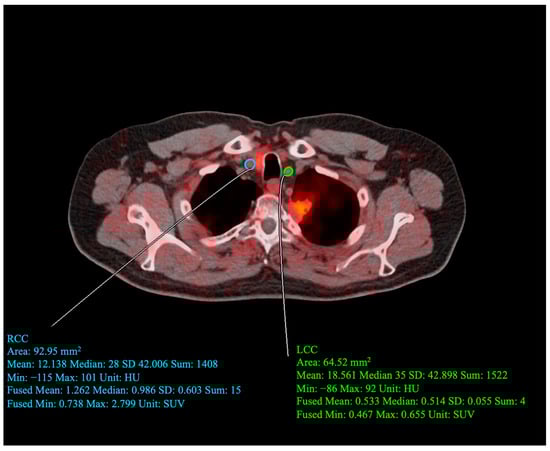

2.5. Carotid PET/CT Acquisition Protocol

2.6. Carotid PET/CT Data Analysis